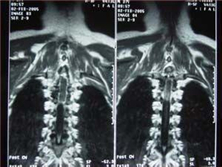

髓内肿瘤

脊髓肿瘤在脊髓肿瘤中并不少见。髓内肿瘤基本分为两类:一类是原发性髓内肿瘤;另一类...